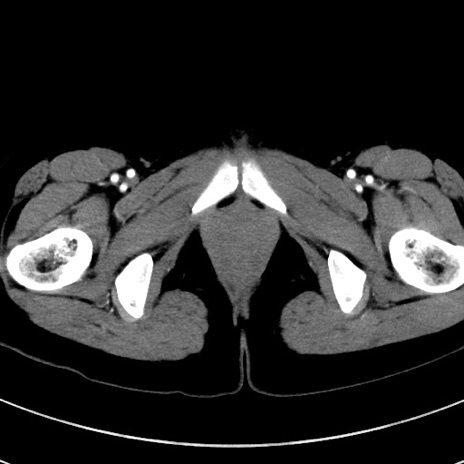

冠状断像

【症例】20歳代女性

【主訴】嘔吐、下腹部痛

【現病歴】昨日夕食後に嘔吐し下腹部痛が出現。本日になっても嘔吐持続し改善しないため来院。

【身体所見】意識清明、BT 37.2℃、BP 108/67mmHg、腹部:平坦、やや硬、下腹部正中から右にかけて圧痛あり、反跳痛軽度あり、tapping pain(+)。

【データ】WBC 13600、CRP 14.94